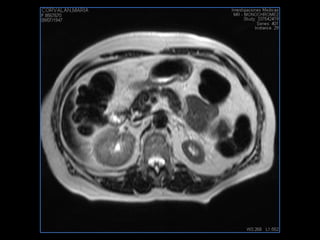

PROTOCOLO hígado graso AXIAL in phase y out phase AX T1 y AX fat sat +SAG T2  CON   GADOLINIO :  COR T1+AX T1(DIN) SAT: NO  FASE: RL THK: 4MM  COIL:  GAP: (FACTOR 1.4)  FOV: 40 CM NEX:2 SINCRONIZACION RESPIRATORIA EN 3 O 4 CICLOS ALE

resonancia de abdomen